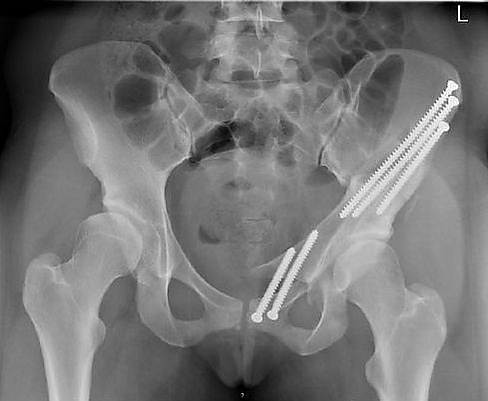

- рентгенографию органов таза;

Травмы мочеполовых и тазовых органов возникают как во время прямой травмы живота или таза (контузии или ранения), так и на фоне переломов таза — острые края костных отломков повреждают тазовые органы в момент травмы, во время транспортировки пострадавшего или сопоставления отломков. Для передне-задней компрессии таза характерны отрыв простатической части уретры, ушиб и разрыв мочевого пузыря, разрыв мышц тазового дна; для боковой компрессии — разрыв перепончатой части уретры и повреждение прямой кишки. Травмы тазовых органов сопровождаются массивным кровотечением, повышают риск инфекционных воспалений; повреждения кишок и мочевыводящих путей приводят к каловым или мочевым флегмонам, абсцессам, остеомиелиту костей таза[2].